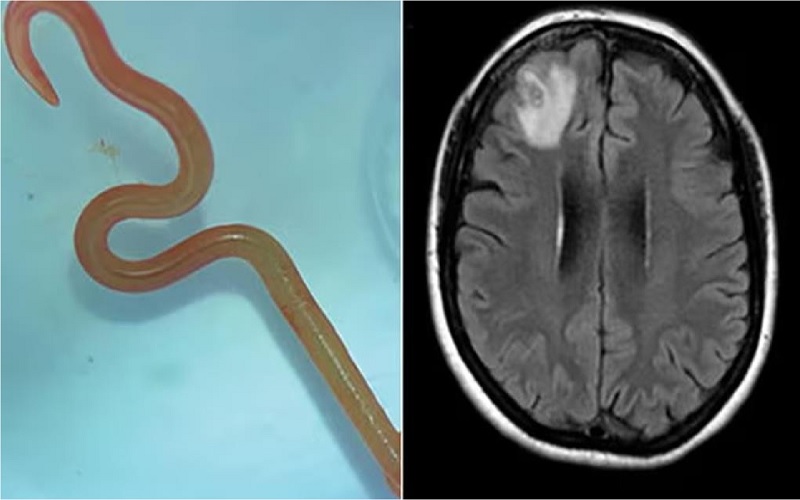

Verme com 8 cm é encontrado em cérebro humano: “Está vivo e se mexe”

O caso inédito ocorreu no hospital de Canberra, na Austrália (Foto:© Reprodução Canberra Health).

O neurocirurgião, Dr. Hari Priya Bandi, retirou um verme parasita de 8 centímetros de comprimento do cérebro de uma paciente, o que a levou a procurar Senanayake e outros colegas do hospital para obter conselhos sobre o que fazer a seguir.

Segundo o jornal The Guardian, a paciente já tinha sido internada em janeiro de 2021 com queixas de febre, dores abdominais e diarreia incessantes, tosse seca e suores noturnos. Em 2022, a estes sintomas juntaram-se sinais de depressão e perda de memória, o que levou ao seu encaminhamento para o hospital de Canberra. Feita uma ressonância magnética que revelava algumas anomalias, a mulher foi operada ao cérebro.

Ophidascaris robertsi é um verme geralmente encontrada em cobras pítons e a paciente do hospital de Canberra marca o primeiro caso mundial do parasita encontrado em humanos.